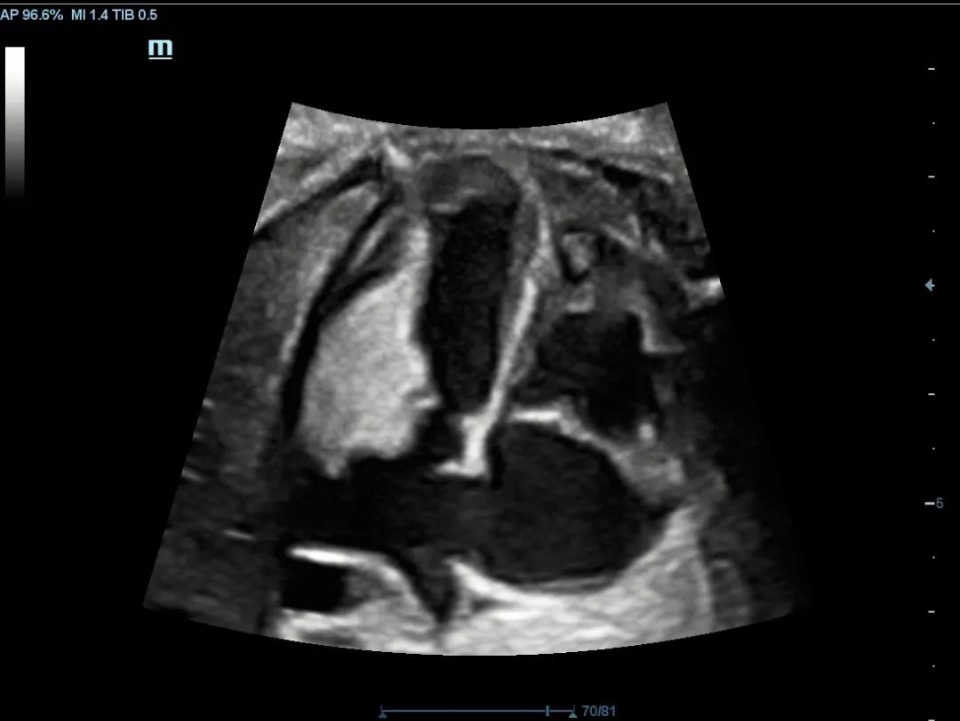

Nodular goiter

ComboWave Transducer Technology

X-Insight provides ComboWave linear transducers for thyroid, breast, vascular and other applications. The transducers utilize a new type of composite piezoelectric material to dramatically optimize the acoustic spectrum and reduce acoustic impedance, allowing clinical experts to experience outstanding performance with extreme image resolution and uniformity.